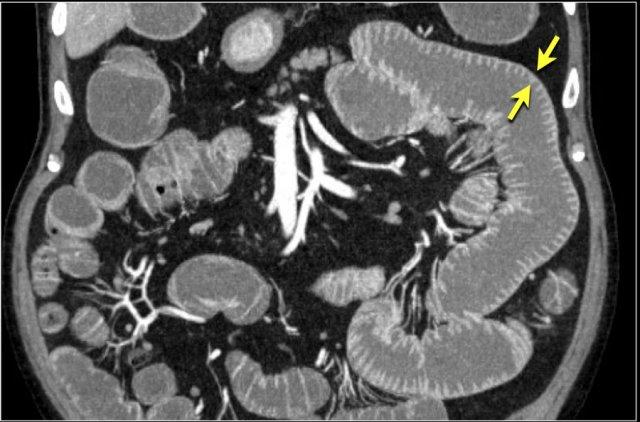

Đây là một bệnh nhân khác bị thiếu máu cục bộ một đoạn dài ruột non do tắc ruột quai kín.

Một đặc điểm hình ảnh quan trọng của tắc ruột quai kín là hình ảnh các quai ruột non giãn xếp theo kiểu nan hoa bánh xe với các mạch máu mạc treo hội tụ về một điểm trung tâm.

Các dấu hiệu thiếu máu cục bộ trong tắc ruột quai kín tương tự như ở các bệnh nhân có nguyên nhân thiếu máu cục bộ mạc treo khác:

- Dày thành ruột

- Phù nề mạc treo ruột

- Cổ trướng

- Sự ngấm thuốc của thành ruột trong thiếu máu cục bộ có thể bình thường, tăng do hiện tượng tái tưới máu, hoặc giảm/mất ngấm thuốc như trong trường hợp này.